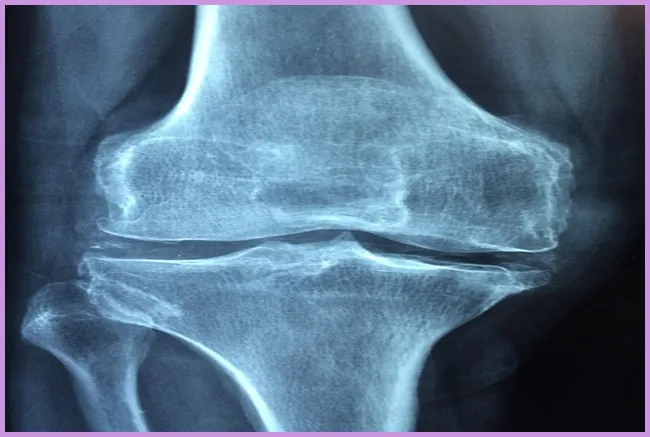

관절 통증의 원인에는 여러 가지가 있습니다. 가장 흔한 원인은 노화입니다. 나이가 들면서 관절의 연골이 마모되고 약해지기 때문입니다. 또한, 유전적인 요소나 자주 사용하는 부위의 과도한 사용도 원인이 될 수 있습니다. 각종 부상이나 외상의 영향도 무시할 수 없습니다.

관절염 진단은 나이와 성별, 가족력 등의 다양한 요소를 고려하여 이루어집니다. 의사는 통증이 발생하는 관절을 검사하며, 필요한 경우 X선 촬영이나 혈액 검사를 통해 확실한 진단을 내릴 수 있습니다. 관절염 치료법으로는 비스테로이드 항염증제(NSAIDs)나 스테로이드 주사와 같은 약물치료가 있습니다.